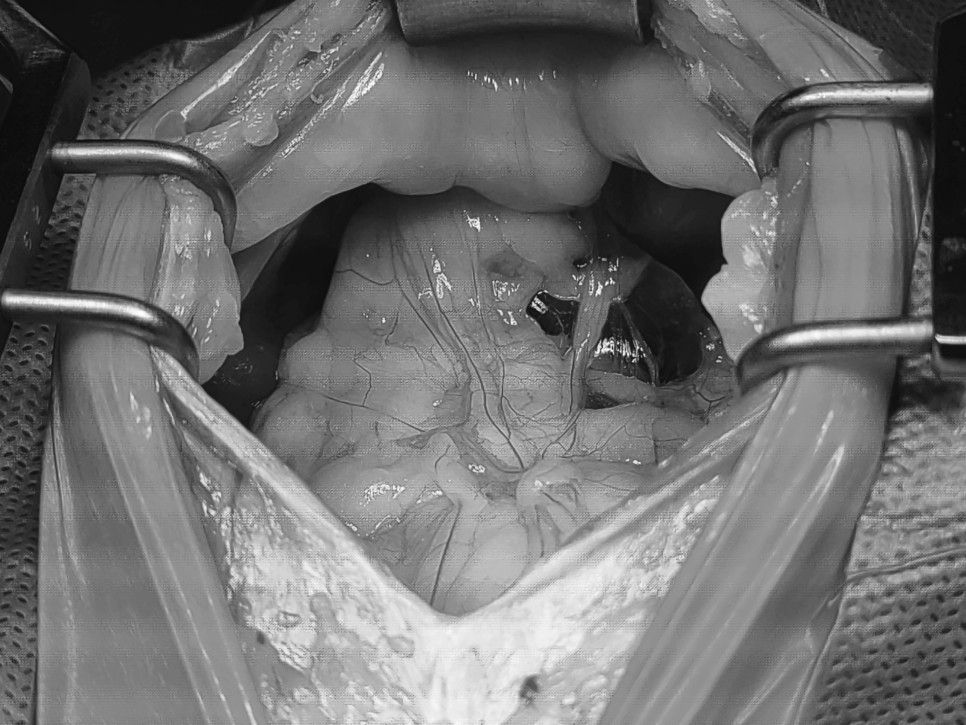

수술

먼저 횡격막의 탈장 부위를 확인하고, 탈장이 된 복강 장기를 원위치로 돌려 횡격막 결손부를 복구했습니다.

선형 이물질에 의해 창자가 꼬여있는 것을 확인하고 나서 패브릭 선형 이물질을 제거했습니다.